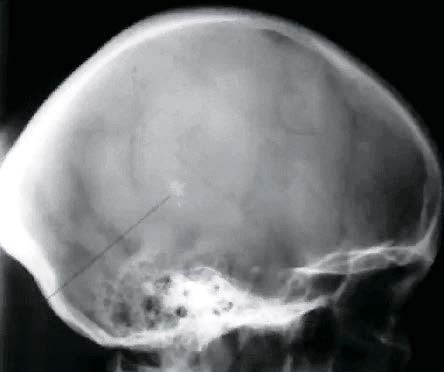

Краниография (рентгенография черепа).

Обнаруживается усиление сосудистого рисунка, расширение диплоических вен, венозных выпускников (см. рис. 2).

Рисунок 2. Обзорная рентгенограмма черепа (краниограмма). Видны расширенные диплоические каналы (признак венозно-ликворной внутричерепной гипертензии).

Анатолий Федин:

Сейчас редко применяют краниографию, когда есть возможность проведения КТ, но даже обычная обзорная рентгенограмма весьма информативна.